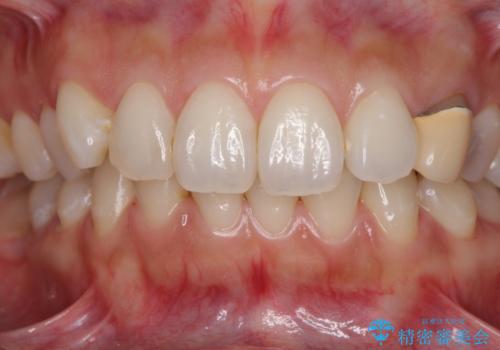

保険診療では樹脂を用いた素材で製作するため、水分が吸収されやすく、一緒に色素が取り込まれるために変色をしてしまいます。

また、裏打ちに主に銀を用いた金属材料を使用するため、金属自体が黒くなったり、イオンとなり溶け出したりして、歯肉ラインが黒くなってしまうことがあります。